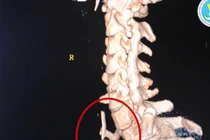

![]() |

| Phim chụp CT sau mổ - Ảnh BSCC |